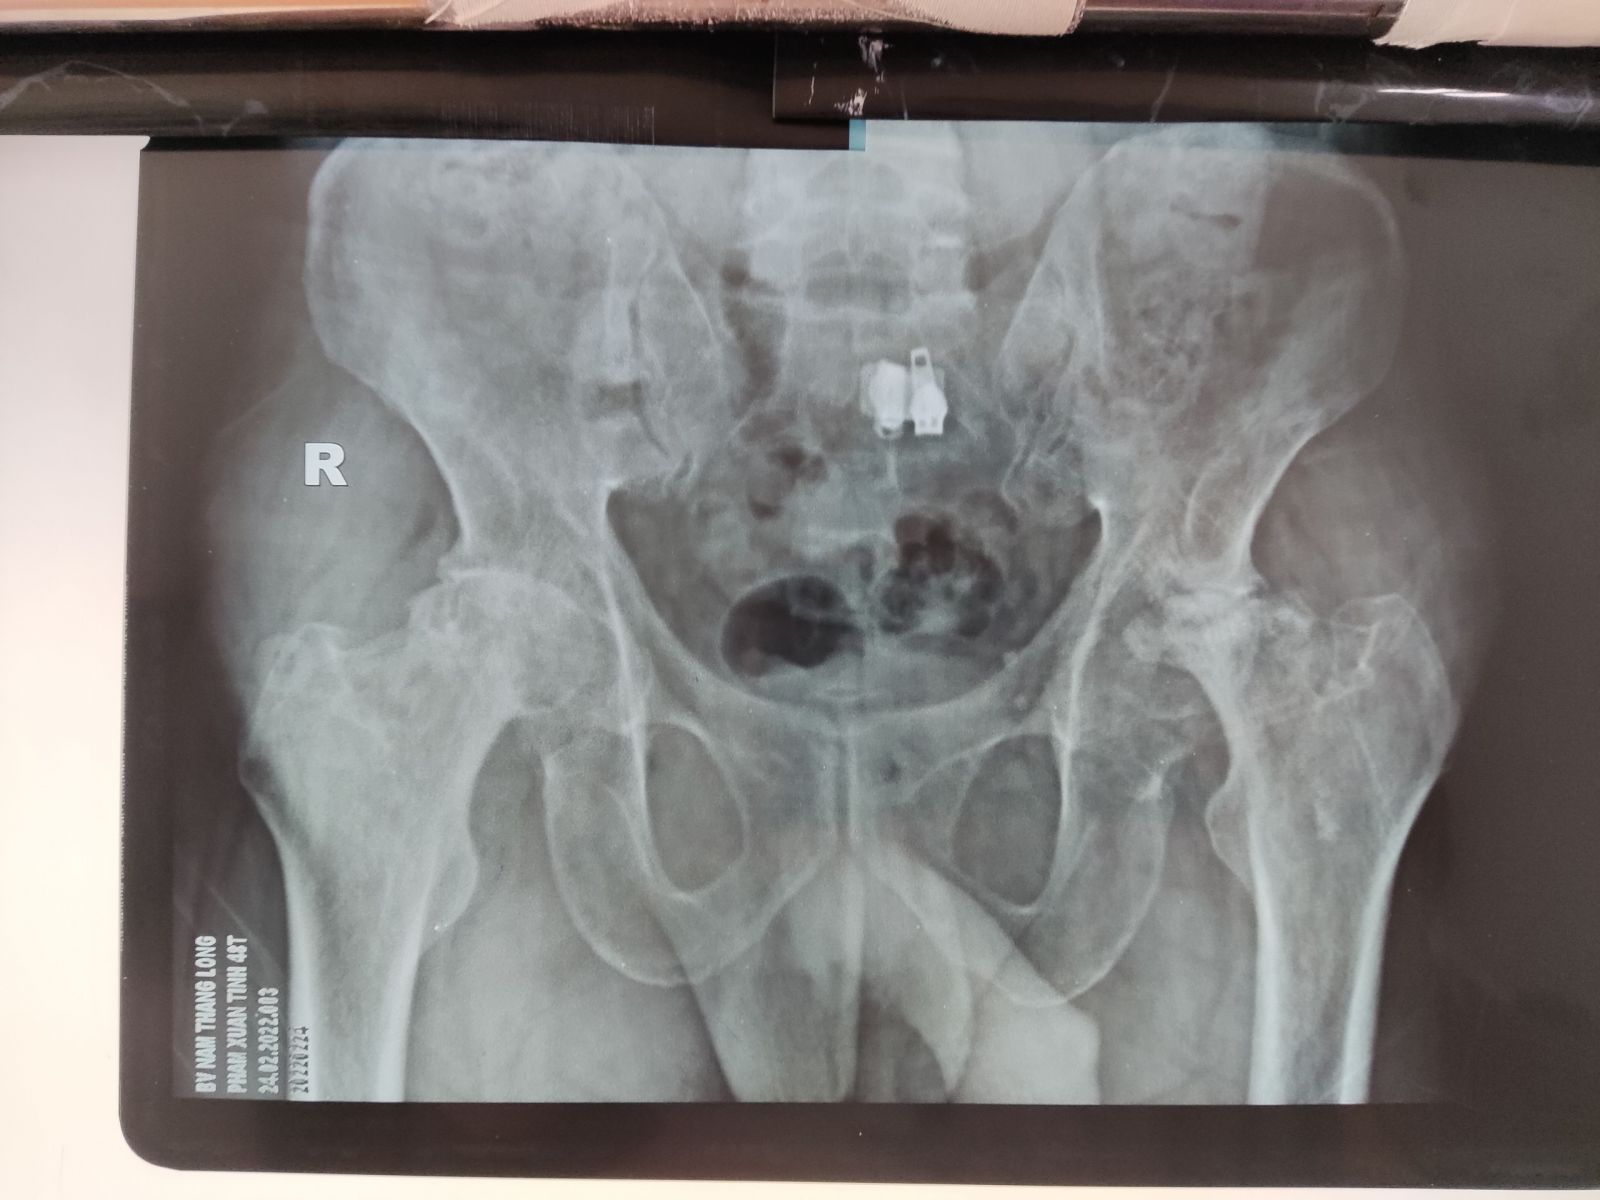

Một số hình ảnh thay khớp háng tại Bệnh viện Nam Thăng Long

Bs. Giang An - Trưởng khoa Chấn Thương Chỉnh hình